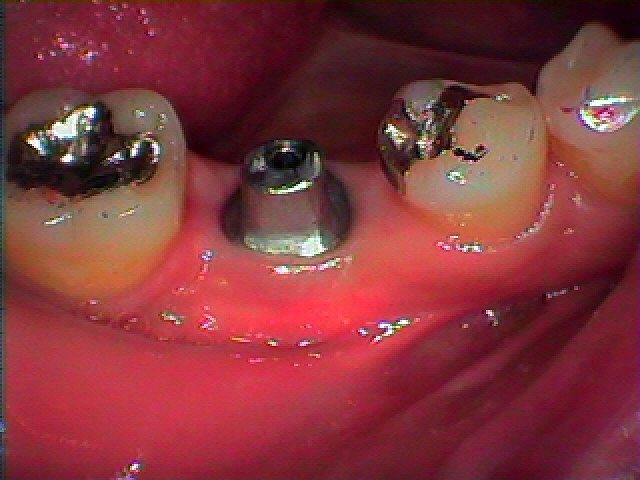

アバットメントと呼ばれる土台を立てていきました

金属が酸化しないように同種金属にて立ち上げています